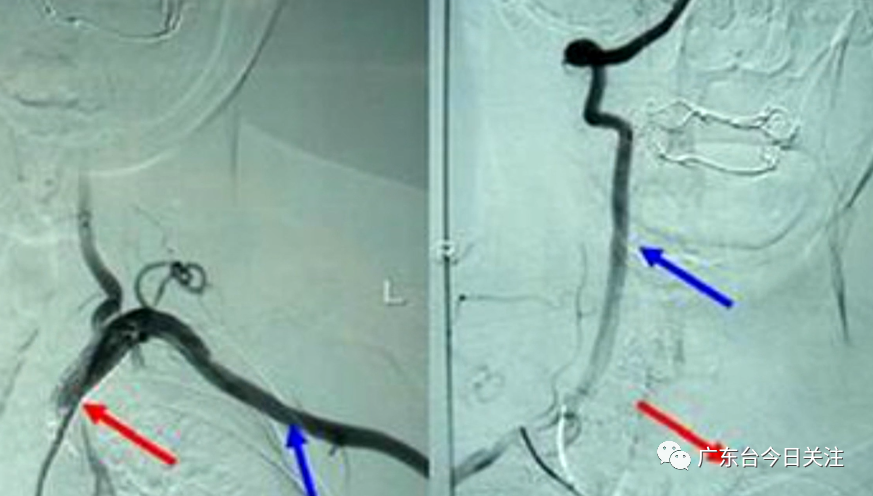

經(jīng)醫(yī)院初步評估,小美的癥狀符合腦卒中,進一步完善頭頸CTA檢查,發(fā)現(xiàn)小美得了一種名叫“東方美女病”,學(xué)名稱為“大動脈炎”的疾病。

經(jīng)過及時手術(shù)治療,小美已經(jīng)恢復(fù)健康。醫(yī)生表示,年輕人群在腦卒中患者中占比達11%,并出現(xiàn)年輕化逐年上升的趨勢。